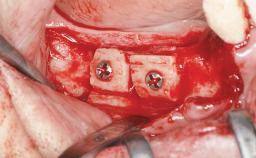

Autologous Block Graft and Guided Bone Regeneration (GBR) for Horizontal Ridge Augmentation in the Posterior Mandible

An 18-year-old man was referred for implant therapy in the posterior mandible to the Department of Oral Surgery and Stomatology (University of Bern, Switzerland). He was healthy and did not smoke. Tooth 35 was congenitally missing, involving a single-tooth edentulous space that offered an adequate mesiodistal dimension for implant placement but exhibited a typical pattern of buccal flattening. A panoramic radiograph was obtained, which revealed a sufficient vertical bone height above the mandibular canal and a normal bone structure in the edentulous area.

Bone Volume Deficient horizontally, requiring prior grafting